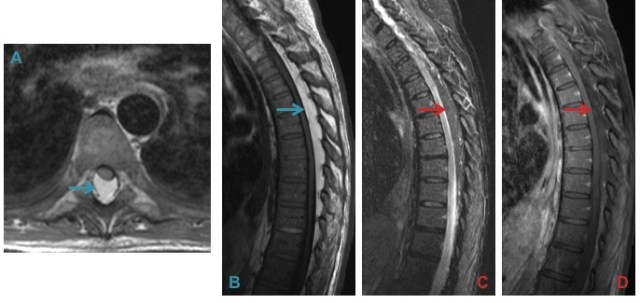

c) Cystic degeneration of herniated discs.

Rare cystic degeneration (A & B) is best identified on fluid-sensitive images (A). Fluid accumulation after disc surgery such as microdiscectomy results in a discal pseudocyst (C & D).